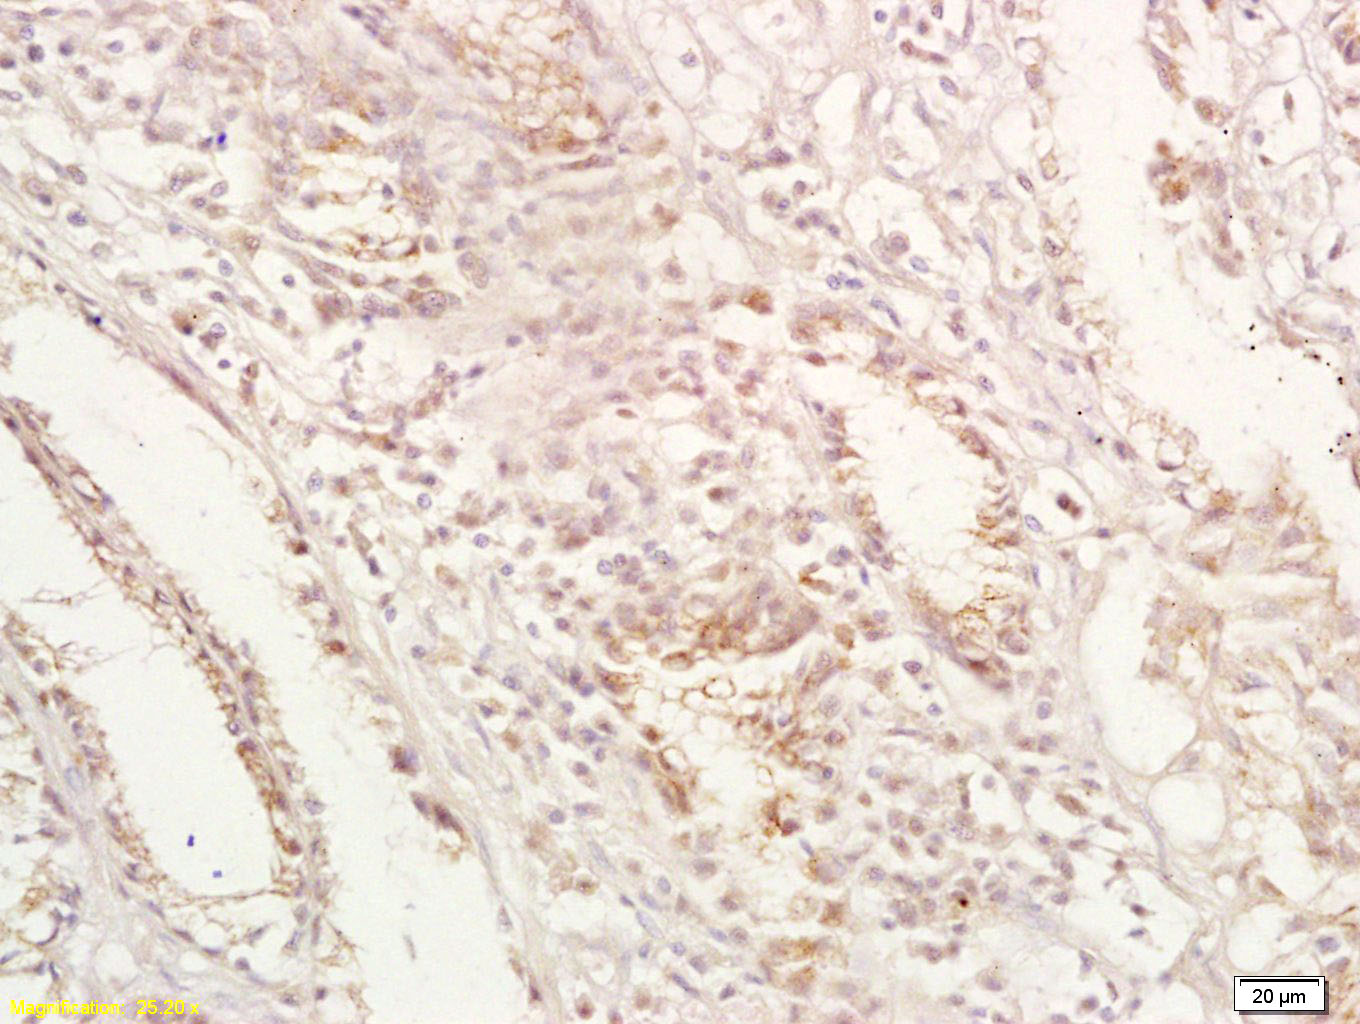

Tissue/cell: human gastric carcinoma; 4% Paraformaldehyde-fixed and paraffin-embedded; Antigen retrieval: citrate buffer ( 0.01M, pH 6.0 ), Boiling bathing for 15min; Block endogenous peroxidase by 3% Hydrogen peroxide for 30min; Blocking buffer (normal goat serum,C-0005) at 37℃ for 20 min; Incubation: Anti-GPA33 Polyclonal Antibody, Unconjugated(bs-1226R) 1:200, overnight at 4°C, followed by conjugation to the secondary antibody(SP-0023) and DAB(C-0010) staining